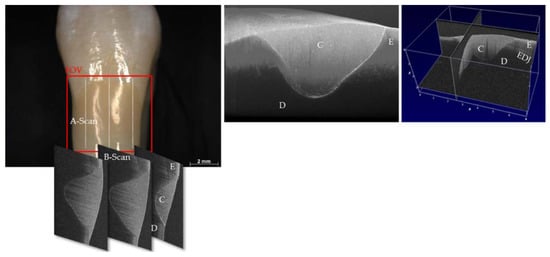

Figure 3. SD-OCT imaging (2D, 3D) of an extracted human premolar restored with composite (C). FOV: field of view, E: enamel, D: dentin, EDJ: enamel-dentin junction.

In contrast, SS-OCT uses a frequency sweeping laser source combined with a photo diode; and SD-OCT applies a wideband laser source in combination with a spectrometer to split the interference signal into single wavelengths. After Fourier transform of the signal, a depth profile of backscattering along a perpendicular line to the object surface is generated (A-scan). The point-by-point scanning of the OCT beam across the sample produces 2D cross-sectional images (B-scans), and the line-by-line scanning generates a series of 2D images from which 3D image stacks can be created (Figure 3). OCT enables images to be generated from the different absorption and scattering of light of various material components in hard and soft tissues. Image contrast arises in areas with structures of different refractive index and light absorption, such as tooth-restoration interfaces, gaps, bubbles, material cracks, or porous areas in carious lesions [8,29,31].